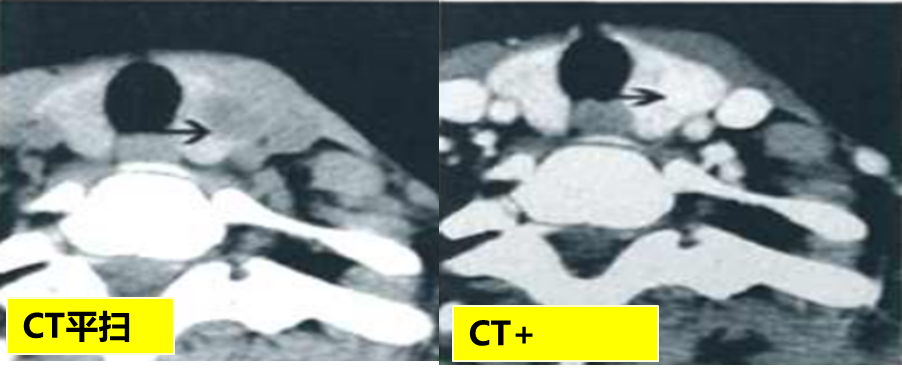

CASE 25 医学百科网 | YxBaike.Com

甲状腺左侧叶髓样癌,平扫边界清晰,增强后边界模糊